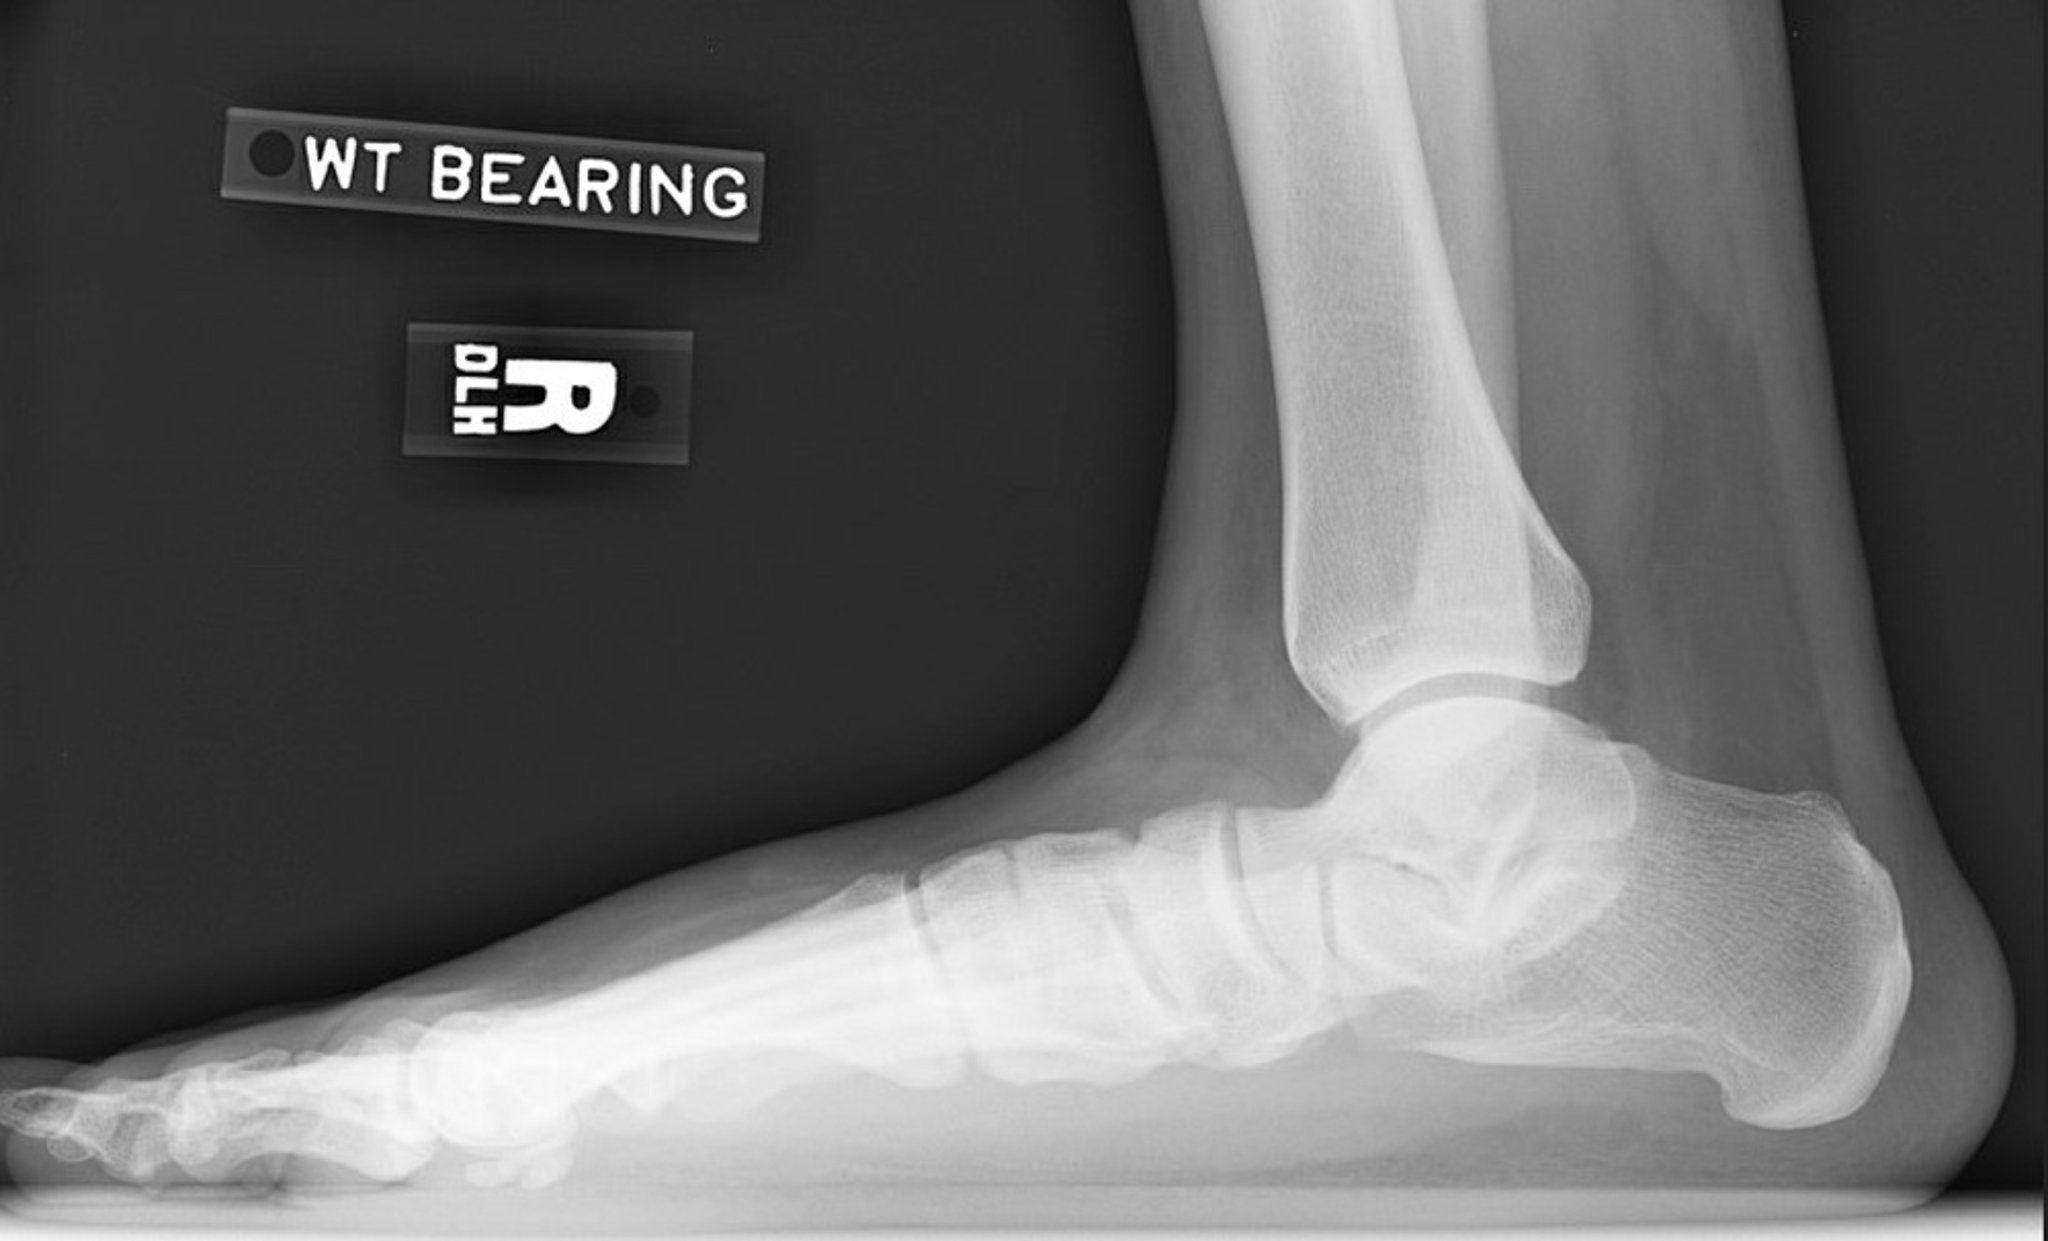

Plattfuß-Röntgenaufnahme

Seitliche Röntgenaufnahme des rechten Fußes mit Verlust der Fußgewölbehöhe. Beachten Sie den verringerten Inklinationswinkel des Fersenbeins und den verringerten Deklinationswinkel des Sprungbeins. Das Subtalargelenk ist verschmälert, aber das Sprunggelenk ist relativ gut erhalten.

Image courtesy of James C. Connors, DPM.